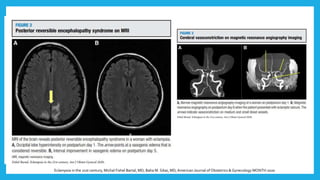

Alteración en la autoregulación en la circulación

cerebral

EdemaVasogénico por

la elevación súbita de la

TA sistólica ≥150 mm Hg

causando hiperperfusión

y edema

Edema Citotóxico por

vasoespasmo

prolongado debido a

una autoregulación

cerebrovascular

Preeclampsia and eclampsia: the conceptual evolution of a syndrome Offer Erez, MD; Roberto Romero, American Journal of Obstetrics & Gynecology FEBRUARY 2022